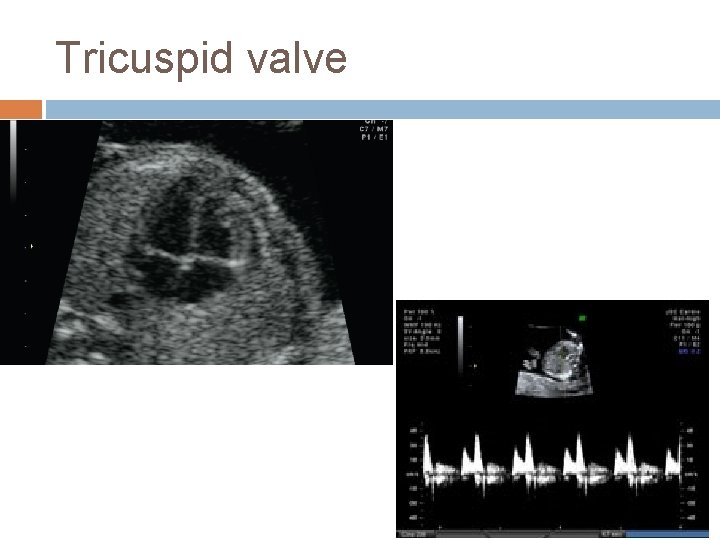

Tricuspid valve

Tricuspid Regurgitation

Interpretation of Tricuspid regurgitation Tricuspid flow Normal Combined Test <1: 50 >1: 50 Anomaly Invasive testing regurgitation Combined Test <1: 50 Other Markers >1: 50 Invasive testing Anomaly & fetal Echo